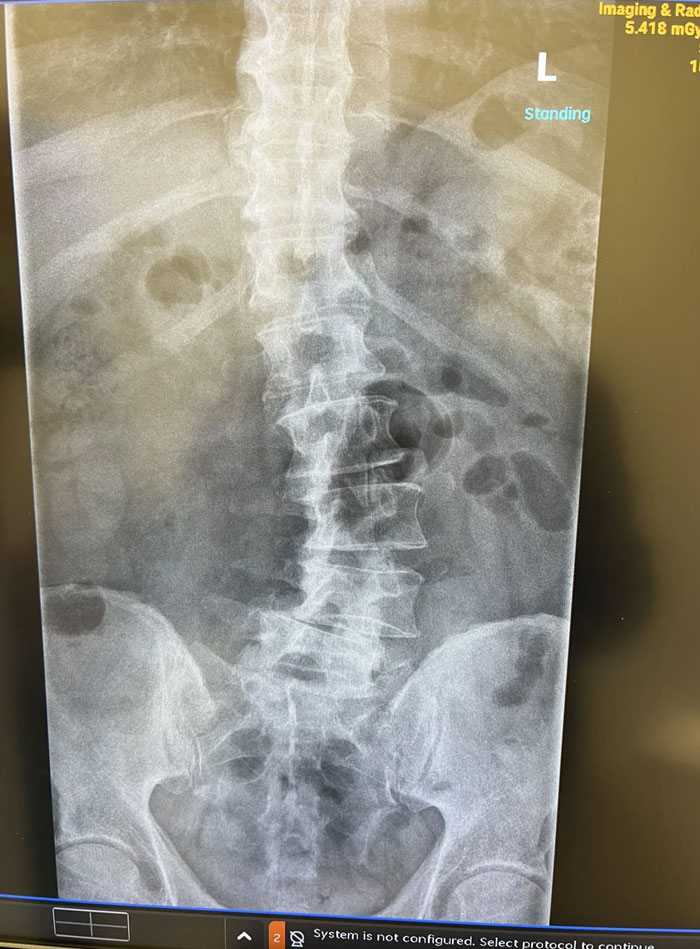

#58 My Dad Said His Back Was Hurting

Image credits: bttby1102